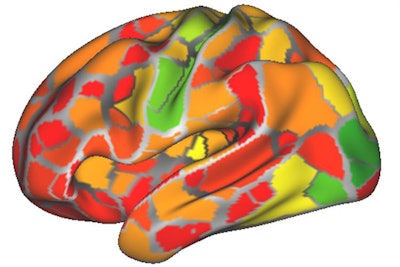

From the data, first author Caterina Gratton, PhD, created a dynamic functional connectivity map of the brain's outer surface and activity changes in 333 regions over time. The goal was to identify areas that became active and inactive in unison. Network maps were also created for each individual, showing patterns of correlation between parts of the brain.